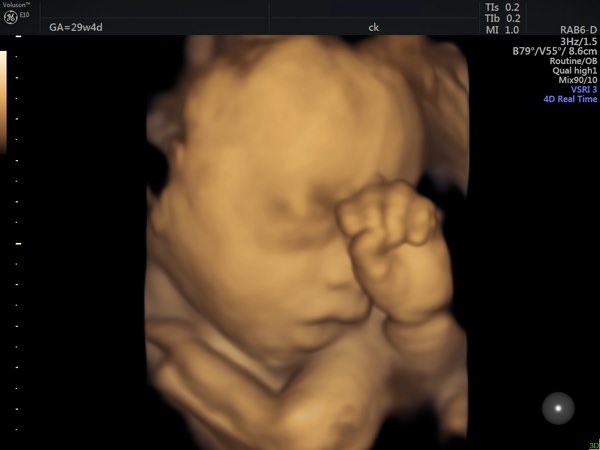

22+ Week Scan

It may also be referred to as a growth scan or late Pregnancy Ultrasound.

Third Trimester Ultrasound (Late Ultrasound) Includes:

• Fetal position.

• Fetal size: an estimated fetal weight is calculated from measuring the fetal head, abdomen and femur.  The weight ‘estimate’ is truly that, with the actual weight usually lying somewhere between 15% above or below the estimation.

• Some assessment of fetal anatomy: bearing in mind, late pregnancy limits the views and the check will not generally be a universal check, like the 19-week ultrasound.